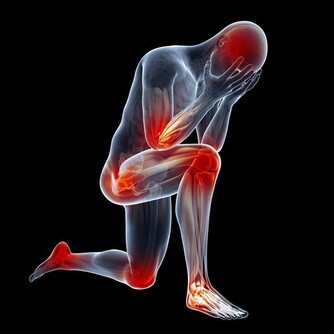

骨質疏鬆即骨質疏鬆症,是多種原因引起的一組骨病,骨組織有正常的鈣化,鈣鹽與基質呈正常比例,以單位體積內骨組織量減少為特點的代謝性骨病變。在日常的生活中,我們最常見的骨質疏鬆的症狀就是骨頭疼痛,身長縮短、駝背,容易骨折,還有就是呼吸功能下降。